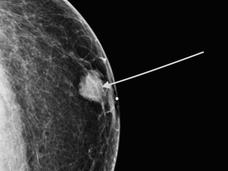

| TMIST Breast Screening Study |

TMIST is a breast screening clinical trial that compares two types of digital mammography: 2-D and 3-D. Learn why this trial is important, who can take part, and how to enroll. |